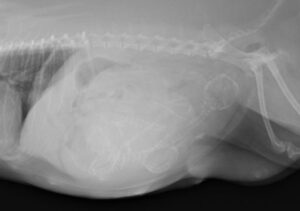

5~6歳以上の去勢手術をしていないオス犬に多い病気ですが、メス犬や去勢した犬に起こることもあります。お尻の筋肉が萎縮した結果、筋肉の隙間から直腸や膀胱が皮膚の下にとびでてしまいます。これにより便が出にくくなったり膀胱炎になったりします。手術をすることで機能回復および今後の致死的な状況を回避することができます。当院では去勢手術→結腸固定→前立腺固定→骨盤隔膜構成筋の縫縮→内閉鎖筋フラップ→浅臀筋フラップの順で通常腹側・臀部左右両側同時に行います。また老化以外に、筋肉が萎縮する原因があったり、腹圧がかかる原因があったりする場合も多いので、再発防止のためそれらの診断・治療も重要です。今回のワンちゃんも無事手術も終わり元気に退院しました。よかったね。